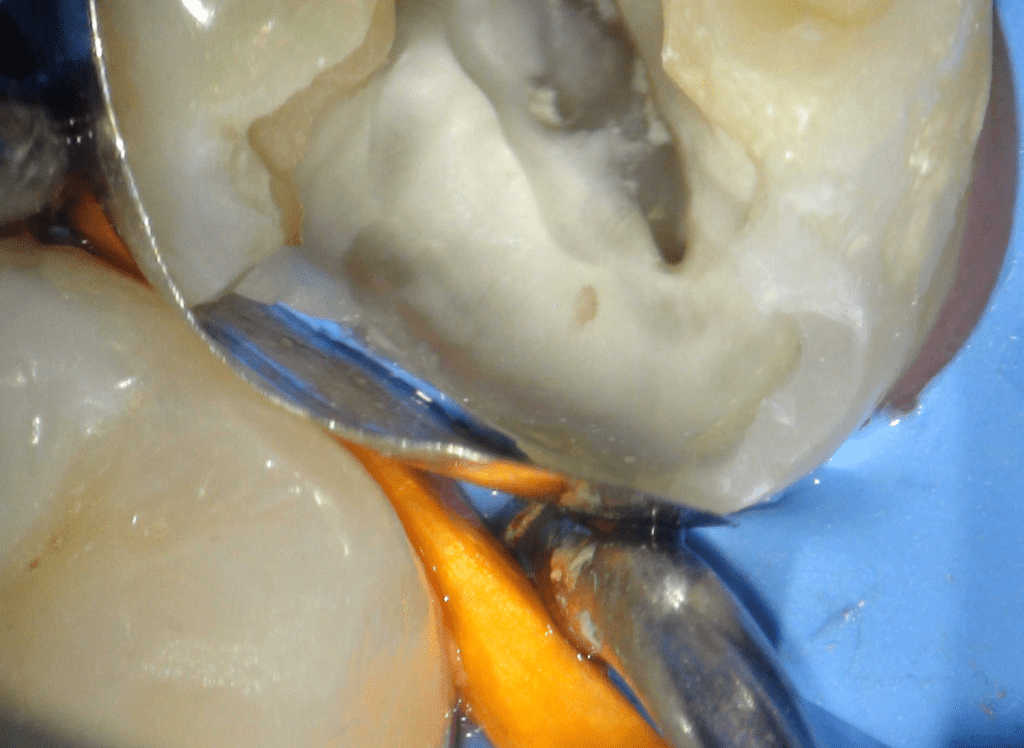

Fisura, remoción amalgama para explorar